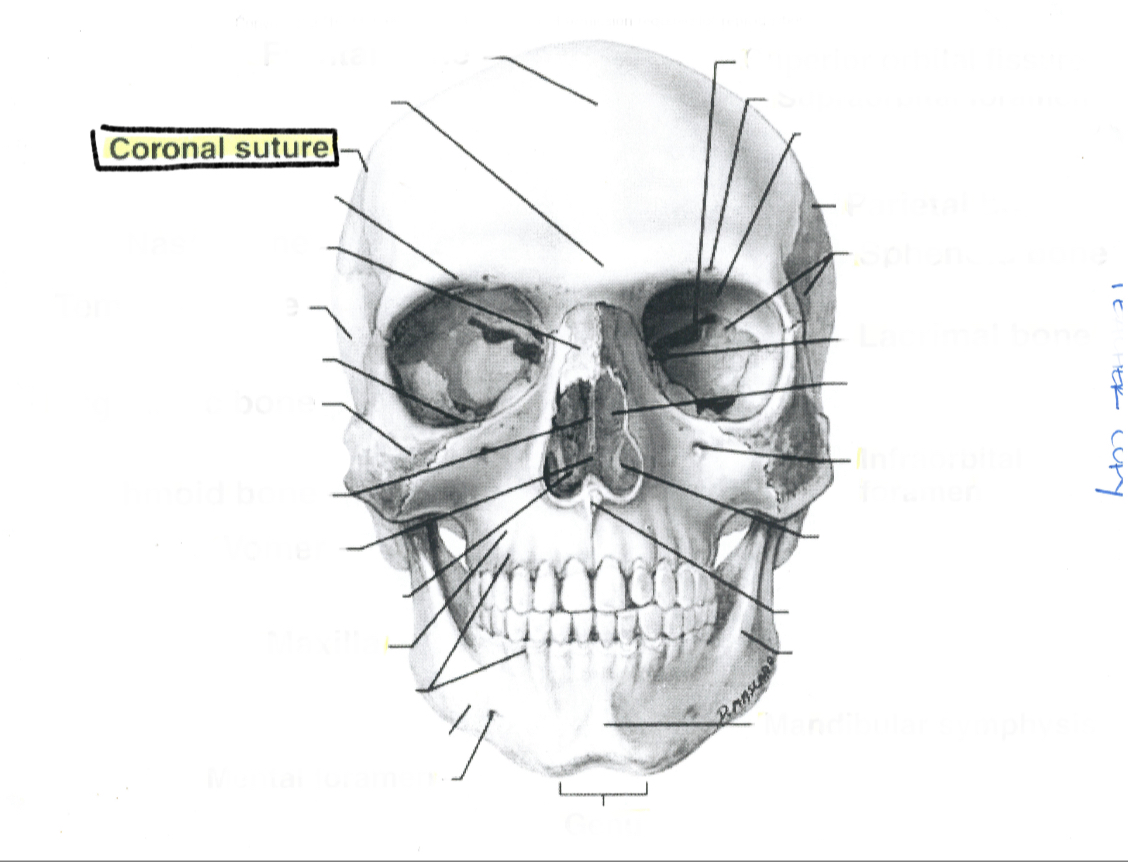

Coronal suture

What is this?